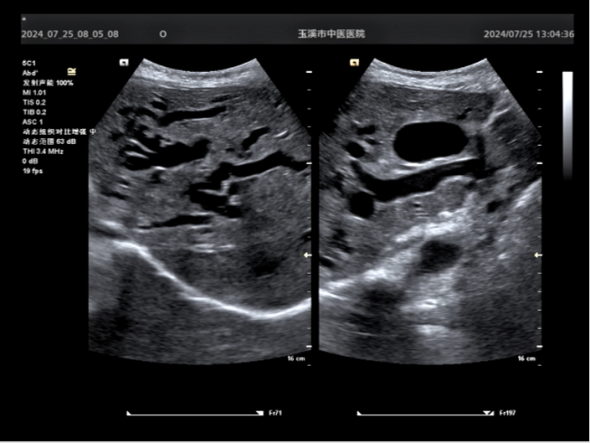

患者女性,因惡性腫瘤致膽道梗阻,術(shù)前MRCR、彩超報(bào)告:胰頭占位,肝內(nèi)外膽管擴(kuò)張,查體和檢驗(yàn)表現(xiàn)為全身黃疸和肝功能損害持續(xù)加重,若不及時(shí)進(jìn)行膽道引流減壓,可能因肝功能衰竭和感染中毒性休克危及生命。經(jīng)科室緊急討論和多學(xué)科專(zhuān)家會(huì)診,一致認(rèn)為應(yīng)及時(shí)行經(jīng)皮肝穿刺膽道引流術(shù)(PTCD),以達(dá)到“減黃”緩解膽道壓力,遏制肝功能持續(xù)惡化,防范感染中毒性休克,為緩解癥狀體征和后續(xù)診療提供保障。

術(shù)前CT和B超顯示肝內(nèi)外膽管擴(kuò)張